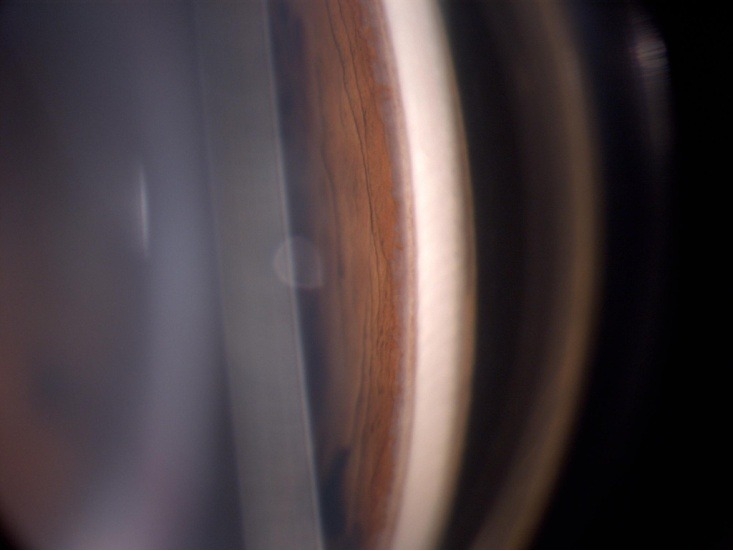

6. 用条状裂隙光线与角膜成10°-20°方向投照,因为光带是通过镜面反射到对 侧房角上的,故镜面所反映的房角形态与实际位置相反。房角镜旋转一周,整个房角的情况可顺次看清。观察内容包括房角的结构、宽窄度、开与闭,以及有无粘连、新生血管、异物或肿块等。